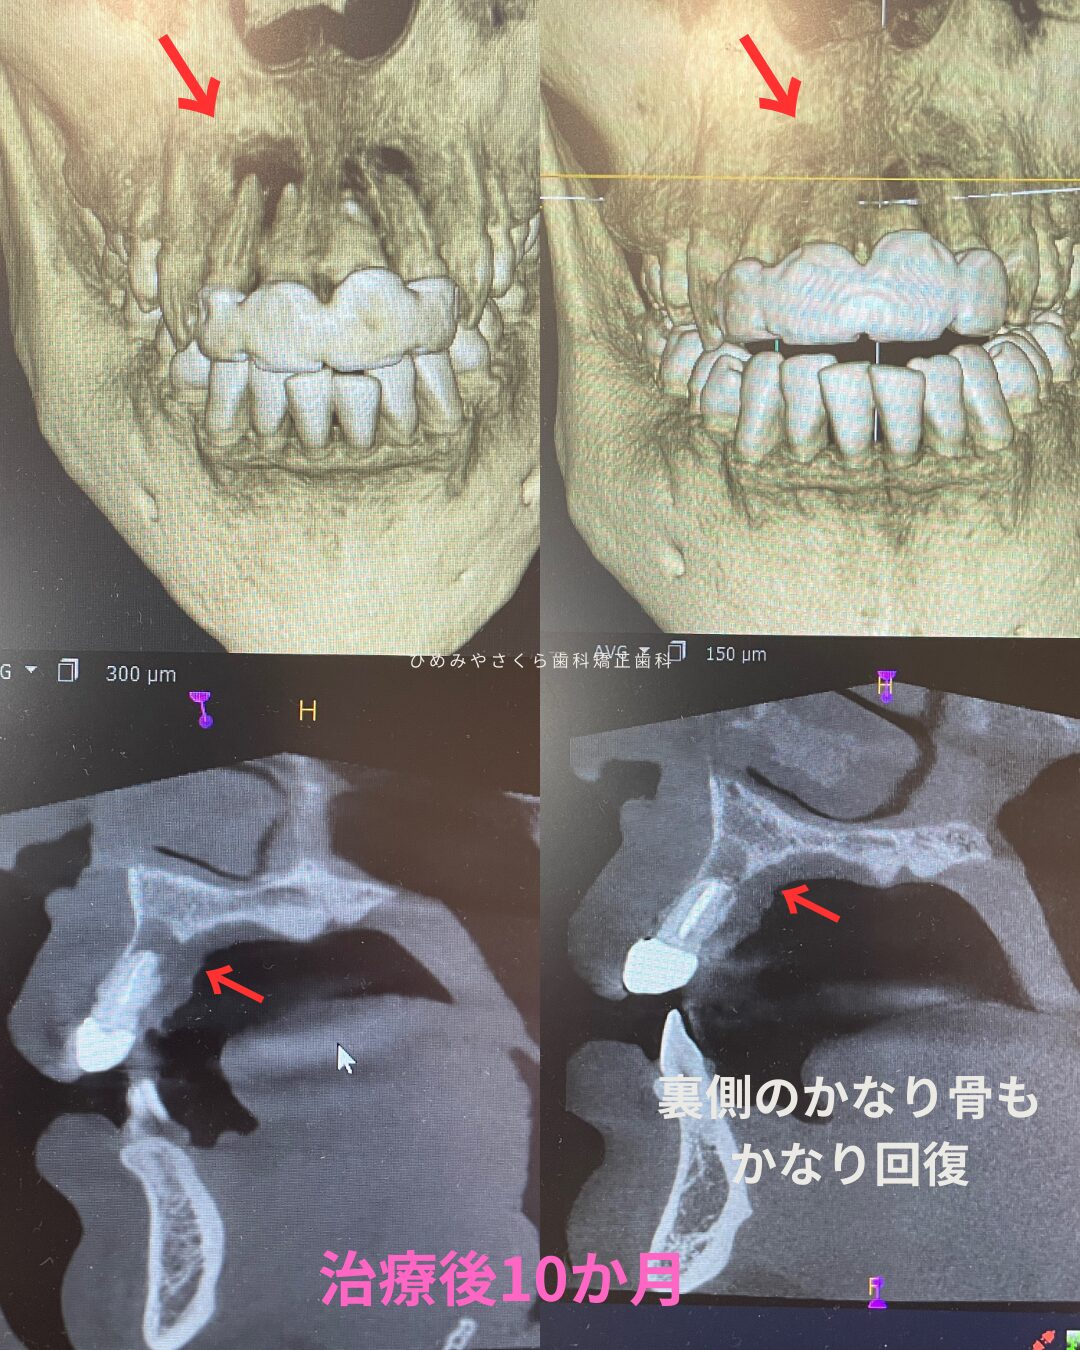

初診時の状態

20代女性。他院で大臼歯の虫歯から神経治療をしたが炎症が治らず当院にご相談くださいました。三重県からご来院で、精密根管治療をご希望です。

上の右奥の歯ぐきにニキビ様のものが出来ています。これもなかなか治らないとのことでした。デンタルレントゲンやCT検査の結果、大臼歯の根3本とも先端に膿がある状態でした。根管治療も中途半端な状態で仮の蓋が詰めてあるだけでした。

初診時のデンタルレントゲン・CT画像

精密根管治療

ラバーダム防湿を行い、マイクリスコープ下での治療です。近心の根には2つの根管があります。この第2根管は裸眼の治療では高頻度で見落とされる傾向にあります。CTを事前に撮影しておくことで複雑な歯の神経の道を事前に把握することは非常に重要です。

治療後

頬側の膿の出口は綺麗に治りました。また保険治療では神経治療した歯歯大きく削りクラウンという被せ物で補われますが、ご本人様のご希望にてダイレクトボンディングで歯の形を作り上げています。

第2根管までしっかりと根管充填が出来ていることがわかります。また上顎洞粘膜の腫れも軽減していることがわかります。